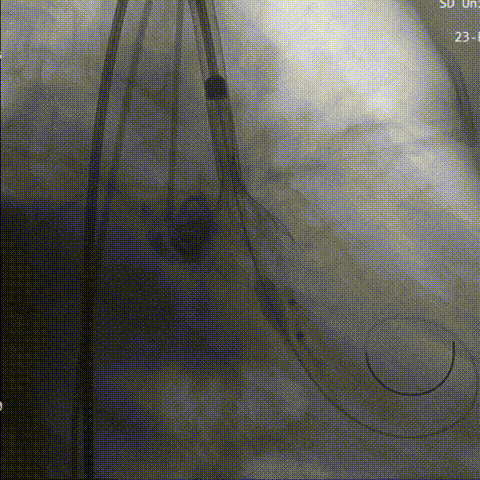

回收后第三次进行瓣上2mm定位,确定释放位置稳定后没缓慢是放到工作位,猪尾导管造影显示无反流。

第三次定位

工作位评估

最后三分之一瓣膜稳定脱钩,造影显示,无明显瓣周漏及反流,瓣膜形态佳,工作稳定。

瓣膜完全释放

猪尾造影评估